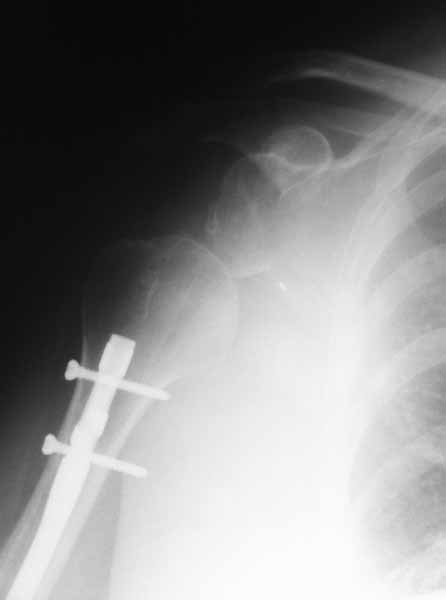

Прошу прощения за отсутствие всех рентгенограмм.

Выбрасываю. По поводу гипсовой повязки: пациентка находилась в повязки типа Дезо. Плечо в приведении.

После БИОС

Плечевой сустав на сегодняший день спустя 10 мес. после травмы.